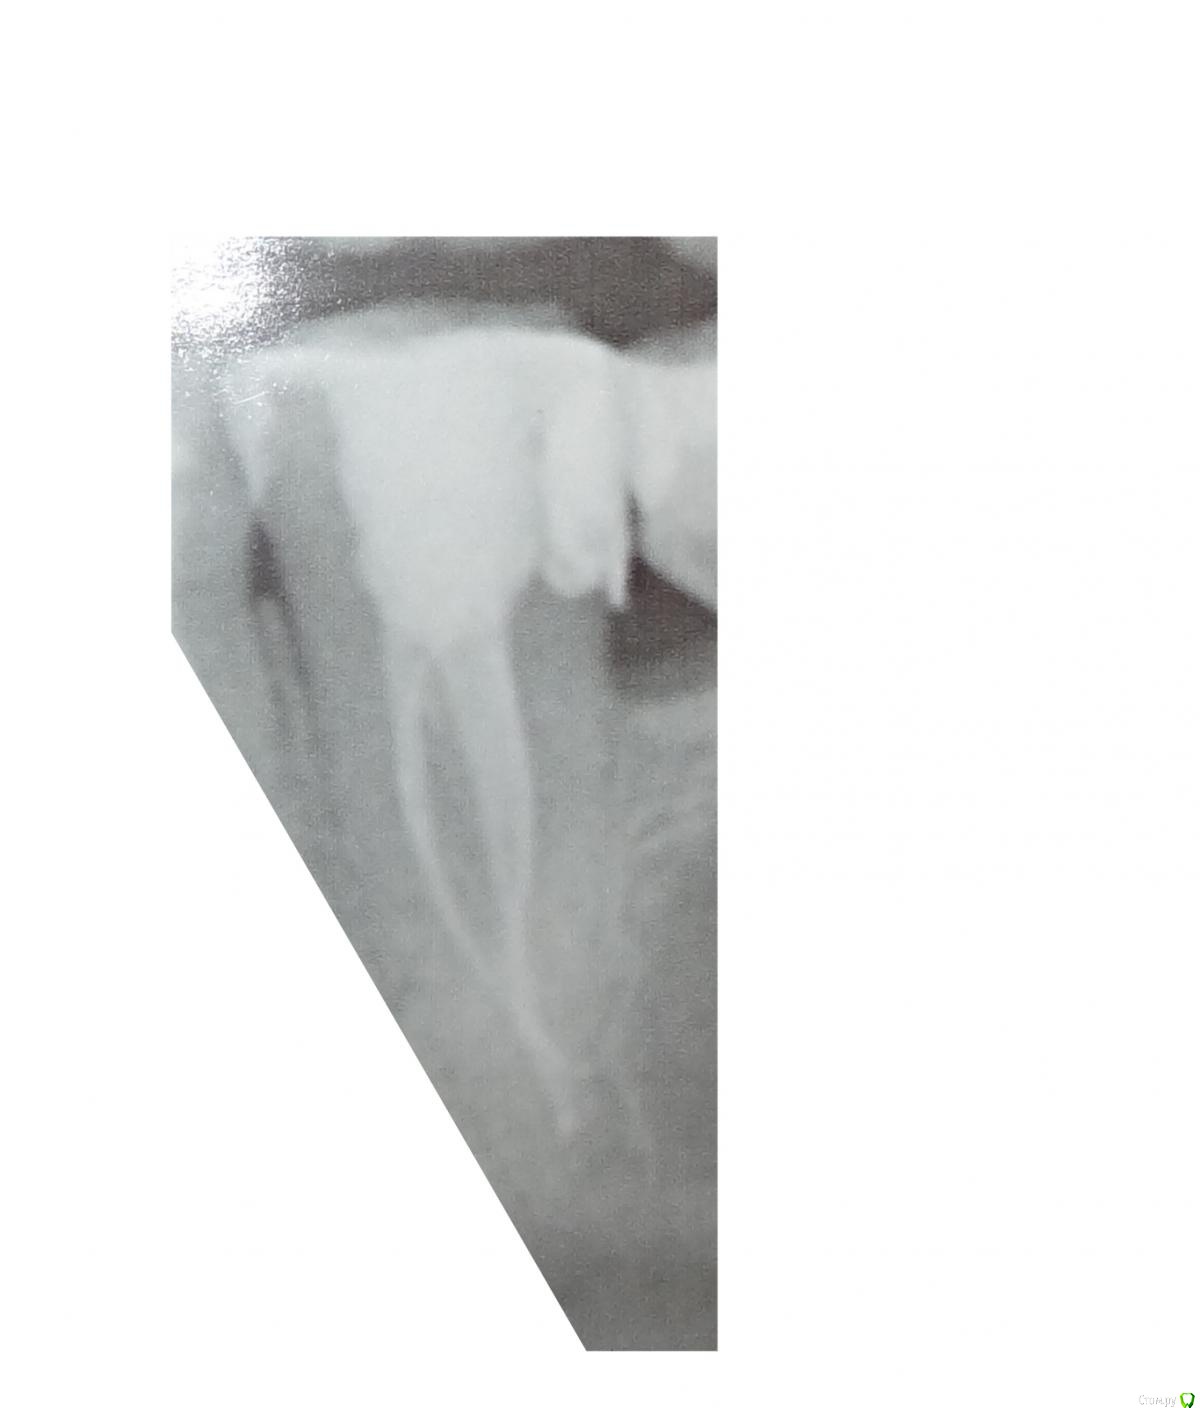

Mikalaika Опубликовано 8 июня, 2020 Автор Поделиться Опубликовано 8 июня, 2020 Это 2D снимок (фотографии сделаны с распечтки на фотобумаге) Ссылка на комментарий

St. Опубликовано 10 июня, 2020 Поделиться Опубликовано 10 июня, 2020 По 2д, насколько позволяет рассмотреть качество, все выглядит хорошо Ссылка на комментарий